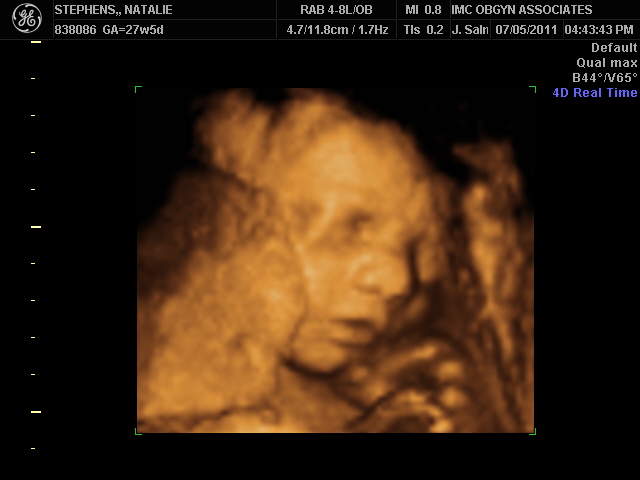

Last week, Jeremy and I got a little sneak peek of Gracie. We had our 4D ultrasound and we think she looks just like big sister, Ella Claire! I took EC's 4D pictures with us, so we could compare immediately and so far, from what we see, they look just alike. That means, I'm going to have another baby that looks just like her daddy! That's okay with me, though! :)

A profile shot in 4D.